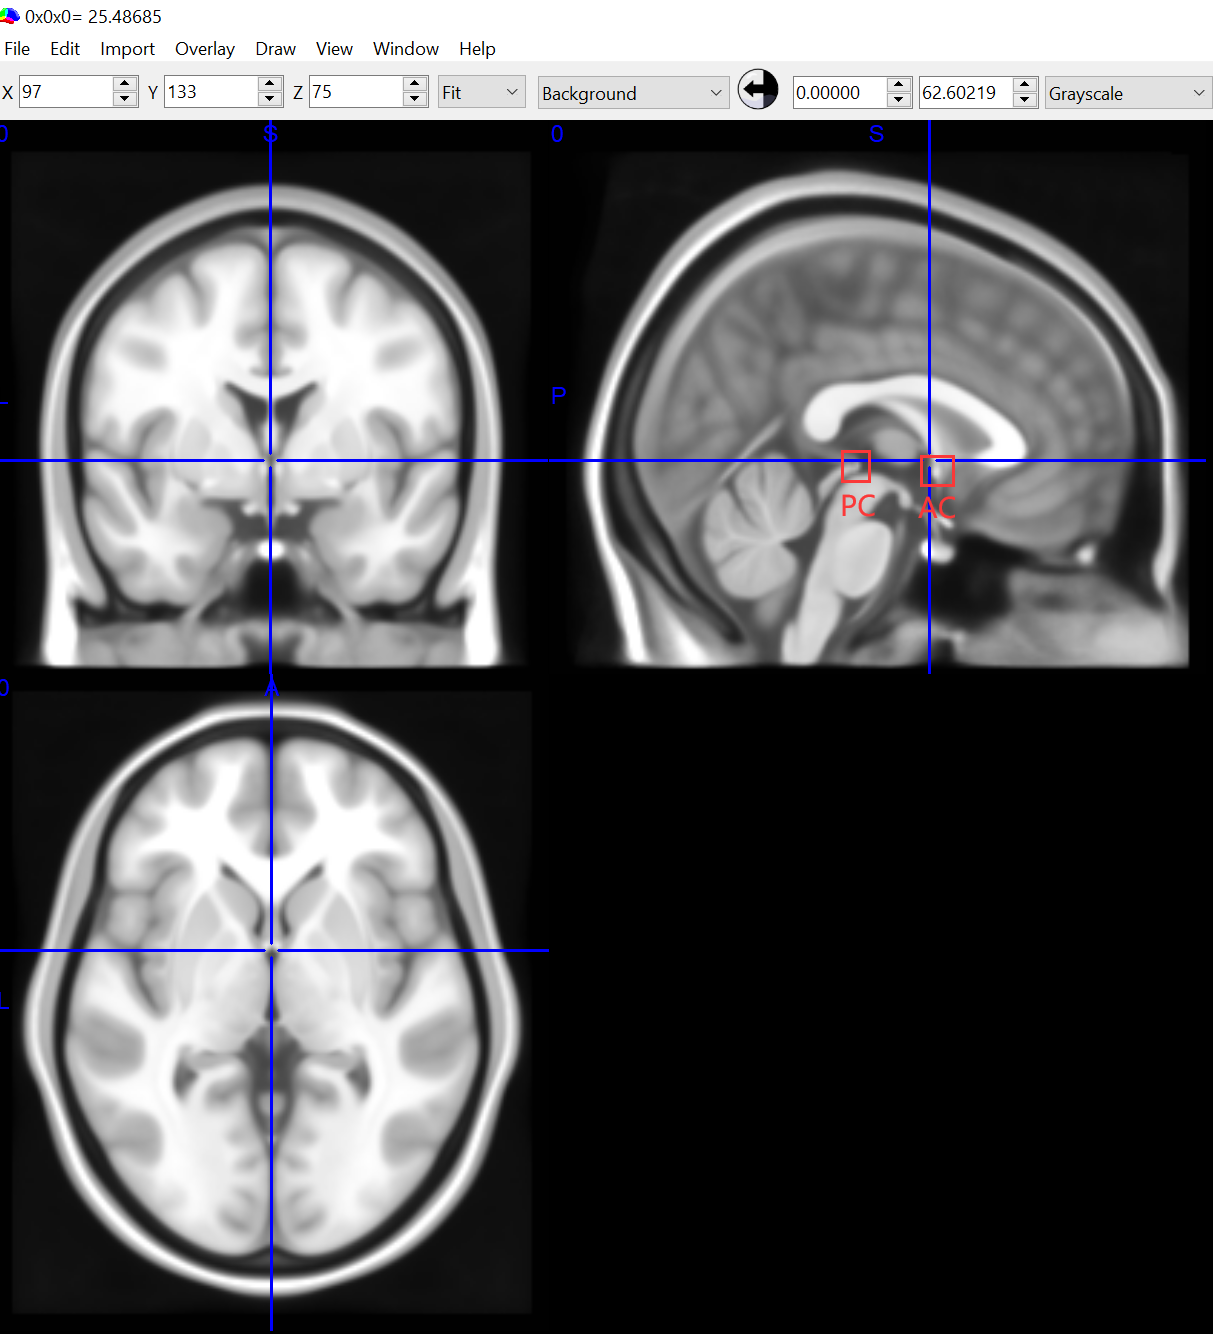

ICBM 152是MNI的标准版,笔者下载了其第六代非线性对称平均脑立体定向配准模型的Nifti格式文件2 ,然后用MRIcron查看,结果如图2。由于它通过了152个人脑T1扫描图像的平均处理,所以看起来有点糊,不过我们还是很容易的就可以找到前联合AC和后连合PC点。CAT,FSL,SPM都有用MNI空间作为标准模板。

MNI152标准模板

图2.MNI152标准模板

对于坐标空间,我们知道为了描述三维空间中的某个位置,显然我们需要定义一个三维笛卡尔坐标系(空间),扫描时,Diocm转nii时,配准时都有定义这样的一个坐标系。一个笛卡尔坐标系可以通过坐标原点,轴方向和单位长度唯一确定。MNI标准模板坐标空间Y轴线如下图红线所示,图源3,且其X轴Z轴在正中矢状界面上。AC点在Y轴下方约4mm,并且AC和PC几乎水平对齐,AC点靠近坐标原点。

有的空间坐标原点直接是AC,而且AC-PC line直接是Y轴,如Talairach空间。被试影像在和标准模板配准(归一化)的同时,也将其原始坐标空间转换到了标准模板对应的坐标空间。不同的标准模板对应的坐标空间可能会有差异,但是可以相互转换。

MNI152标准模板坐标空间与AC-PC line

图3.MNI152标准模板坐标空间

最后,如果我们用MNI模板,前面提到MNI标准模板对应的坐标空间原点在AC附近,而AC-PC line靠近Y轴,所以如果我们在采集图像的时候,或者配准前手动校正坐标原点(reorientation)的时候,定义原始坐标空间的原点和轴都应该尽量靠近该标准。那样在进行到这一步时,不仅配准的精度,还有配准的速度都会有所增加。

如果配准结果坏掉了,多半是坐标原点离AC太远或者Y轴严重偏离AC-PC line,此时可以用SPM的Display工具,修改位移量,旋转量来重新定义原始空间的坐标原点。当然,如果对配准精度要求比较高,在配准之前也可以用SPM的Display工具处理一下,以减少在非线性配准的优化过程中落入局部最优解的可能,如图5所示。另外,三个位移量分别对应mm:后面的三个值的相反数,最后填完需要点Reorient保存修改。

orientation与AC-PC点

图5.SPM的Display工具